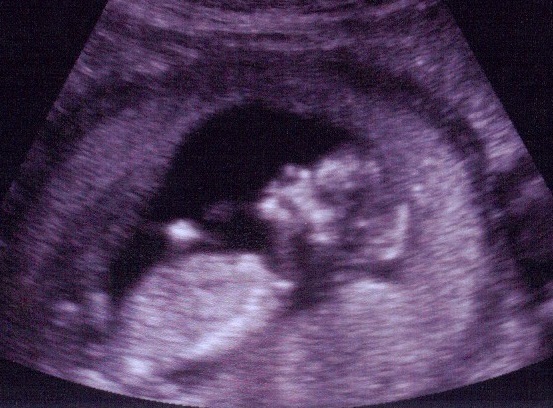

We received our 20 week scan early (at 18wk 4 days) with some 4D photos! The babies are doing great.........and the best news - the "Small choroid plexus cyst reported earlier is no longer seen." Yahoo!!

Twin I

Approx. gestational age is 19 weeks 1 day

BPD - 43mm, HC - 162mm, AC - 137mm, FL - 29mm

EFW: 274gms

Twin II

Approx. gestational age is 19 weeks 5 days

BPD - 46mm, HC - 162mm, AC - 149mm, FL - 31mm

EFW: 316gms

Both show normal vetricular system, fetal spine, limbs, cord insertion, 3 vessel cord, UB, stomach bubble!! Grow Babies Grow!!!!

So.......on to the freaky 4D photos!! I love them but Sandy prefers the regular ultrasound photos!!